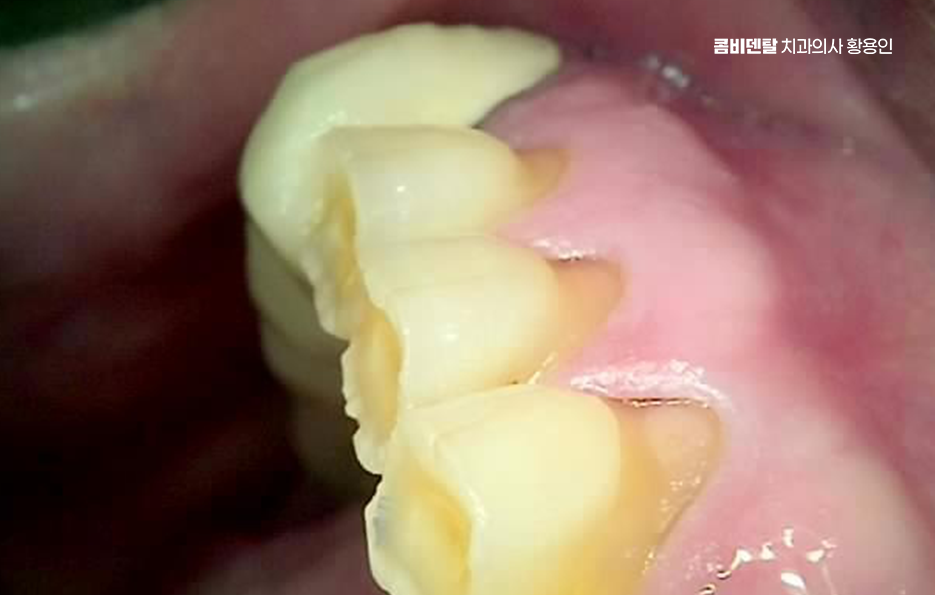

어금니 부위는 씹는 힘이 강한 만큼, 임플란트에 전달되는 하중도 커서 단순히 임플란트를 심는 것뿐 아니라, 그 힘을 어떻게 분산시킬 것인지에 대한 계획이 중요한데 임플란트의 위치, 각도, 크기, 그리고 위에 올라가는 보철물의 형태까지 함께 고려되어야 하며 이 과정이 충분히 고려되지 않으면, 임플란트 자체는 괜찮아 보여도 시간이 지나면서 주변 뼈에 무리가 가거나, 보철물이 깨지는 문제가 생길 수 있어요.

잇몸 상태 역시 중요한 주의사항으로 잇몸에 염증이 남아 있거나, 치주 질환이 제대로 관리되지 않은 상태에서 임플란트를 진행하면 실패 위험이 높아질 수 있었어요.